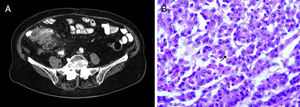

The first case was an 89-year-old woman with no family history of colon cancer. She presented with insidious clinical symptoms of 3-month progression that included anorexia, weight loss, and abdominal pain. Laboratory work-up results reported hypochromic anemia, leukocytosis with no neutrophilia, and elevated C-reactive protein. A computed tomography (CT) scan identified irregular thickening of the cecum, with infiltration of the pericecal fat and the terminal ileum wall, and no signs of obstruction, as well as numerous regional and retroperitoneal adenopathies (fig. 1A). Long colonoscopy detected an ulcerated and strictured mass that took up almost the entire cecal lumen and impeded the passage of the endoscope. Biopsies were positive for signet ring cell adenocarcinoma. Right oncologic hemicolectomy was performed and infiltration at the level of the right parietocolic peritoneum and the mesocolon was observed.

Anatomopathologic report: poorly differentiated adenocarcinoma of the colon with > 50% signet ring cell pattern (fig. 1B) with multiple tumor nodules and countless lymphatic embolisms, disperse tumor implants, and stage T4aN2bM1b (2010 ICC/AJCC TNM classification, 7th Edition). Immunohistochemistry showed microsatellite instability in the PMS-2 and MLH-1 genes. Adjuvant oncologic treatment was rejected.